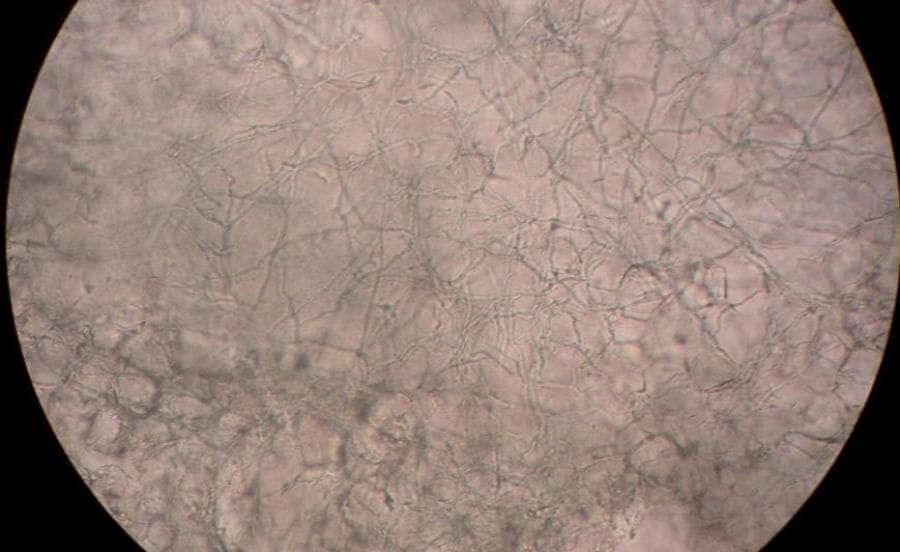

Schimmelinfecties komen in de natuur veel voor, niet alleen bij mensen en dieren maar ook bij planten en voedsel. Denk bijvoorbeeld aan schimmel op brood of kaas. Voetschimmel ontstaat door een infectie met een schimmelsoort die in staat is om de menselijk huid te infecteren. Deze schimmels worden “dermatofyten” genoemd. Voetschimmels voeden zich met materiaal van de buitenste laag van de opperhuid, de hoornlaag. Schimmels planten zich voort door middel van sporen die onder voor hen gunstige omstandigheden weer kunnen uitgroeien tot schimmels.

Hoe ontstaat huidschimmel?

Schimmels en gisten zijn overal. Ze zitten bij iedereen op het lichaam. Dit is meestal niet erg. Op uw huid zit een vetlaagje dat u beschermt en zorgt dat u geen klachten krijgt.

Soms werkt de bescherming van uw huid minder goed. Bijvoorbeeld als het vetlaagje van uw huid eraf gaat. De schimmel komt dan uw huid binnen en kan daar groeien. U krijgt dan plekken op de huid.

De schimmel zit in schilfers van de huid. De schilfers laten los van de huid en komen op bijvoorbeeld de vloeren van zwembaden, doucheruimtes en sportruimtes. Als u deze schilfers op uw huid krijgt, kunt u plekken krijgen.